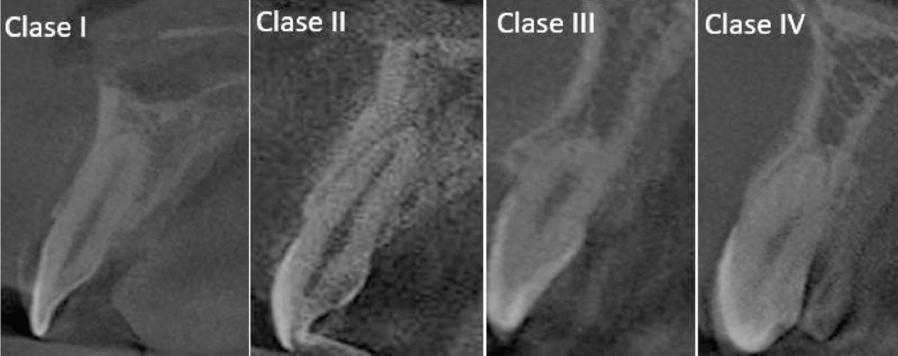

Figura 1. Clasificación de la posición de la raíz sagital (PSR) de los dientes, según lo propuesto por Kan et al., para determinar la posición de la raíz de los dientes anteriores superiores en el plano sagital de una tomografía computarizada de haz cónico (CBCT).

La PSR se clasificó según el protocolo propuesto por Kan:

Clase I: la raíz se posiciona contra la cortical labial.

Clase II: la raíz está centrada en el medio de la cavidad alveolar sin comprometer la cortical labial ni palatina en el tercio apical de la raíz.

Clase III: la raíz está posicionada contra la cortical palatina.

Clase IV: al menos dos tercios de la raíz están posicionados en la cortical labial y palatina (Figura 2)